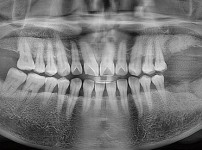

숙면임플란트 3개 - 스트라우만임플란트 (이*웅님)